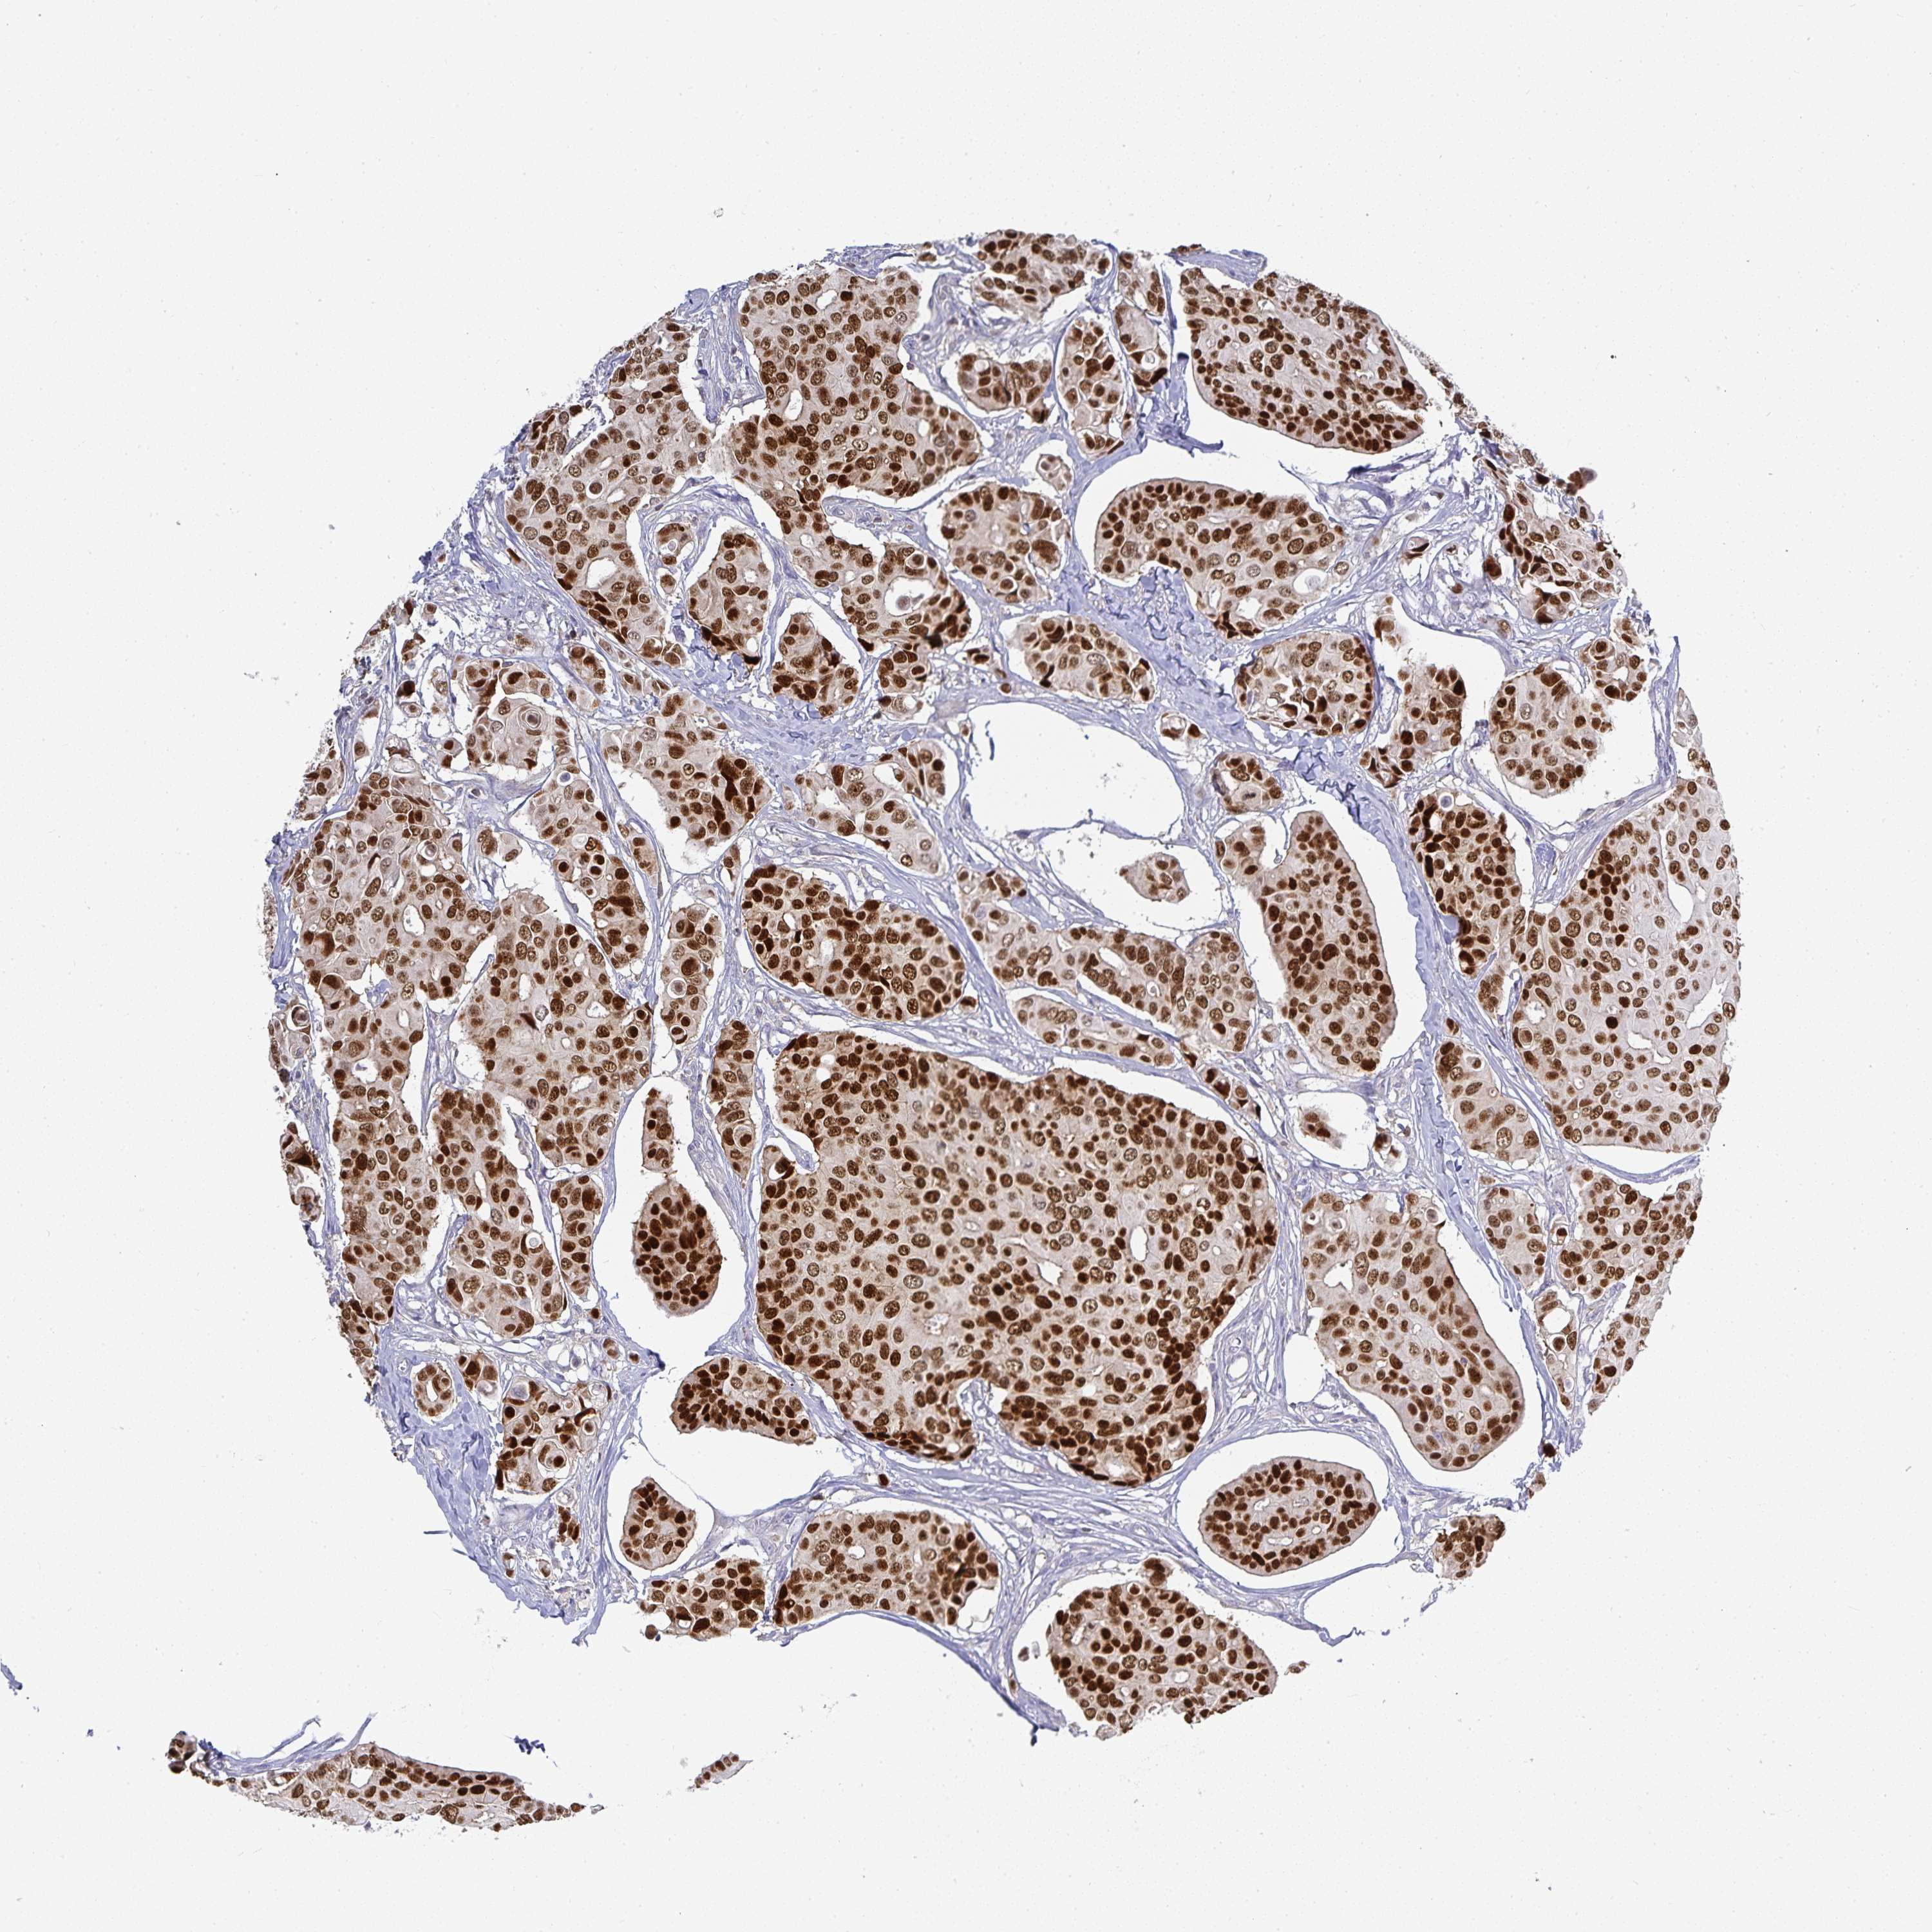

CANCER BREAST CANCER Show tissue menu

BRCA TCGA BRCA VALIDATION PROTEIN EXPRESSION